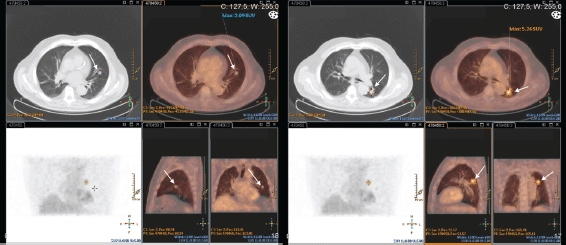

This exam was repeated one month later, and endobronchial lesions were found in the left lung. Biopsy confirmed metastatic adenocarcinoma of the prostate (PSA positive; TTF1, CK7, and CK20 negative). The PET–CT–FDG presented with the expression of two hypermetabolic secondary nodes in apical and anterobasal segments of the lower lobe of the left lung. Many other bilateral nodular lesions were present but without significant hypermetabolic uptake (Figure 4).

Figure 4. Patient #3 PET-CT-FDG: two hypermetabolic nodes in the lower lobe of the left lung – apical and anterobasal segments (arrows).